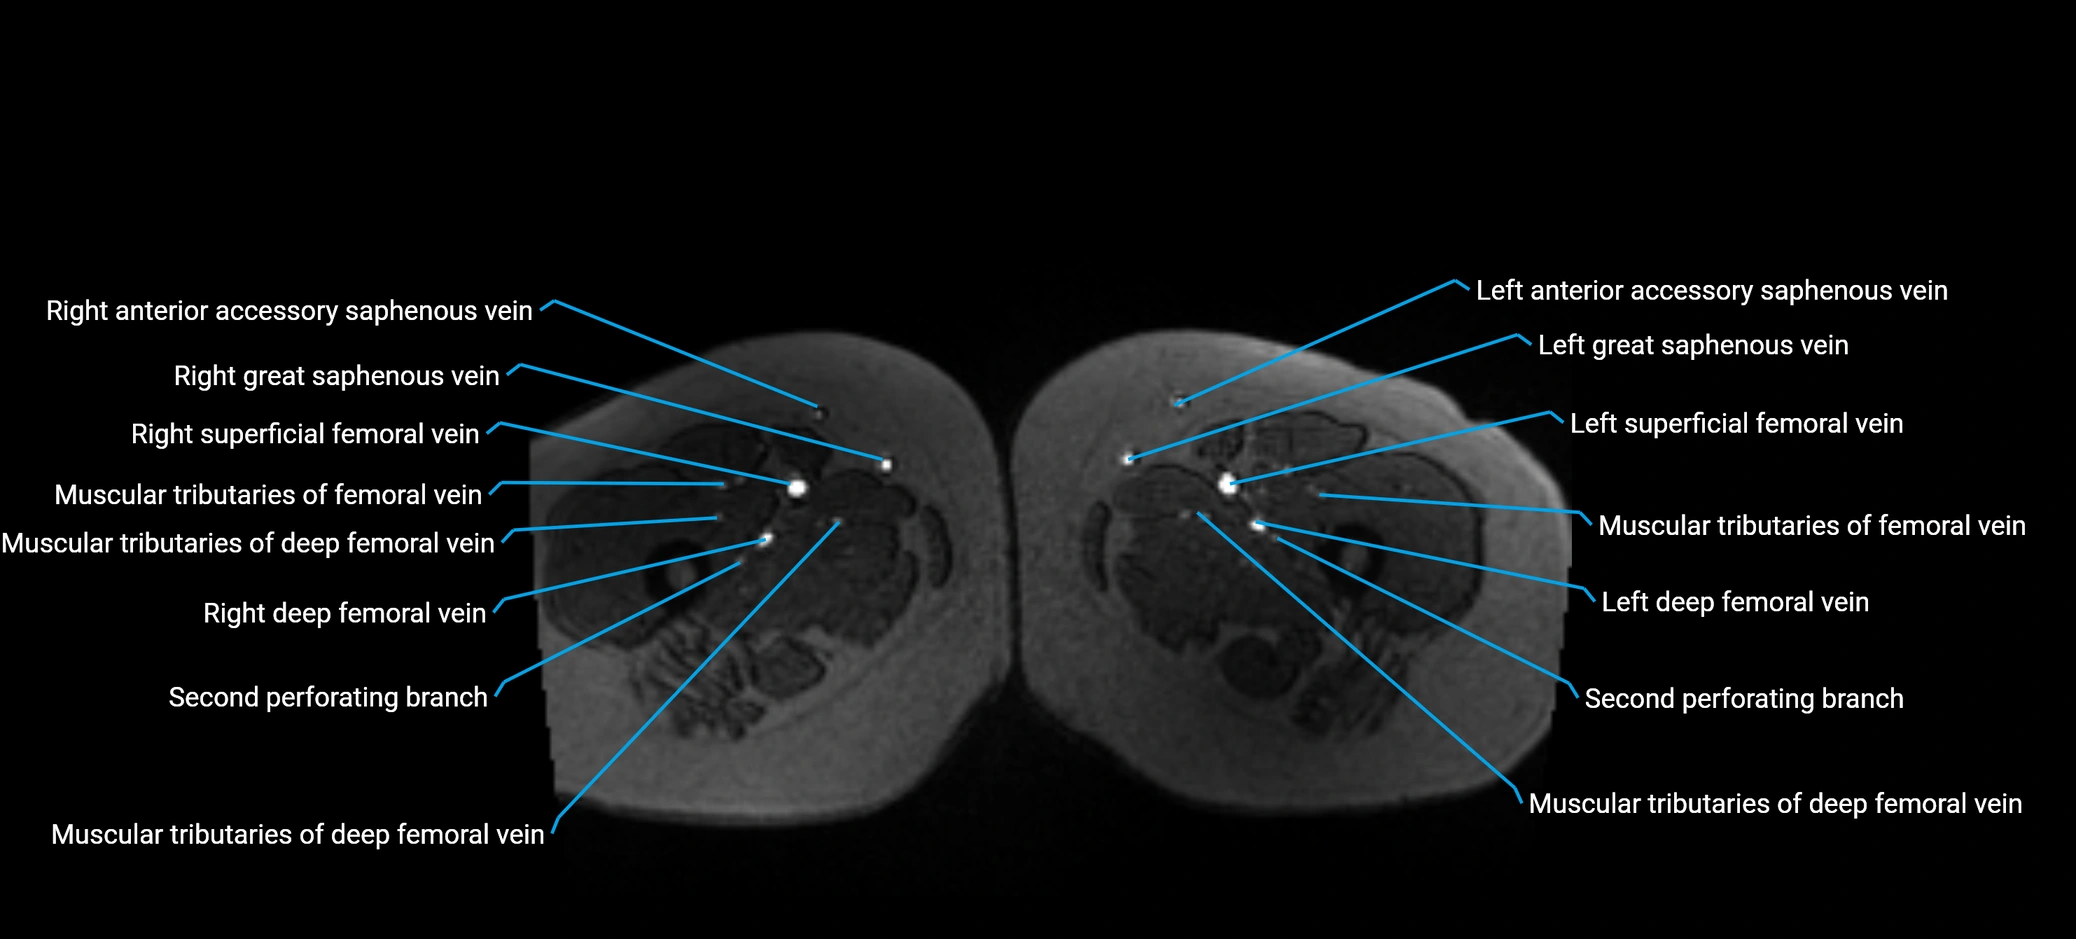

MRI image

image